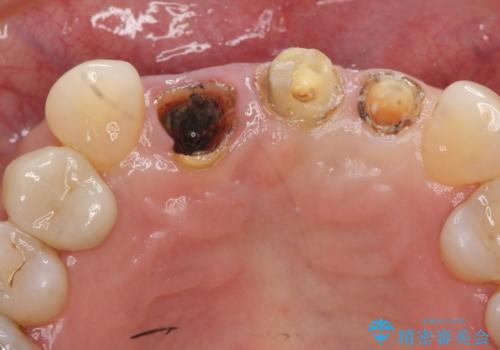

- 下顎前歯部の突き上げで上顎前歯の被せ物が土台ごと外れてしまった方の症例です。

右上1番目の歯は根元まで割れてしまっており、保存不可能だったため抜歯となりました。